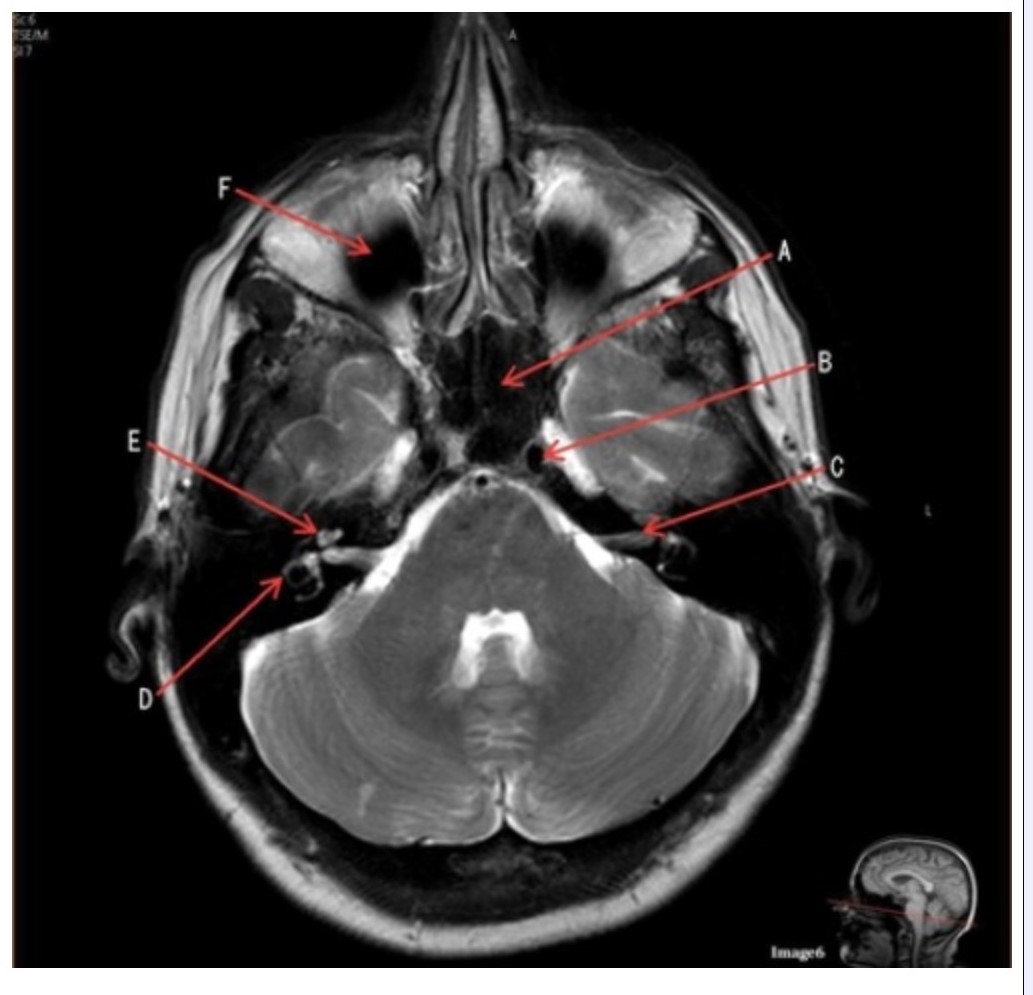

Letter A in Image 6 is pointing to:

A. Maxillary sinus

B. Sphenoid sinus

C. Frontal sinus

D. Internal carotid artery

Letter D in Image 6 is pointing to:

A. 7th cranial nerve

B. Cochlea

C. Trigeminal nerve

D. Semicircular canal

Letter C in Image 6 is pointing to:

A. 7th cranial nerve

B. Cochlea

C. Trigeminal nerve

D. Semicircular canal

Letter B in Image 6 is pointing to:

A. Maxillary sinus

B. Sphenoid sinus

C. Vertebral artery

D. Internal carotid artery

Letter F in Image 6 is pointing to:

A. Maxillary sinus

B. Sphenoid sinus

C. Frontal sinus

D. Optic chiasm

Image 6 is an example of a _____ weighted sequence acquired in the _______ imaging plane.

A. T1; Axial

B. T1; Coronal

C. T2; Axial

D. T2; Coronal

E. STIR; Axial

Letter E in Image 6 is pointing to:

A. 7th cranial nerve

B. Cochlea

C. Trigeminal nerve

D. Semicircular canal